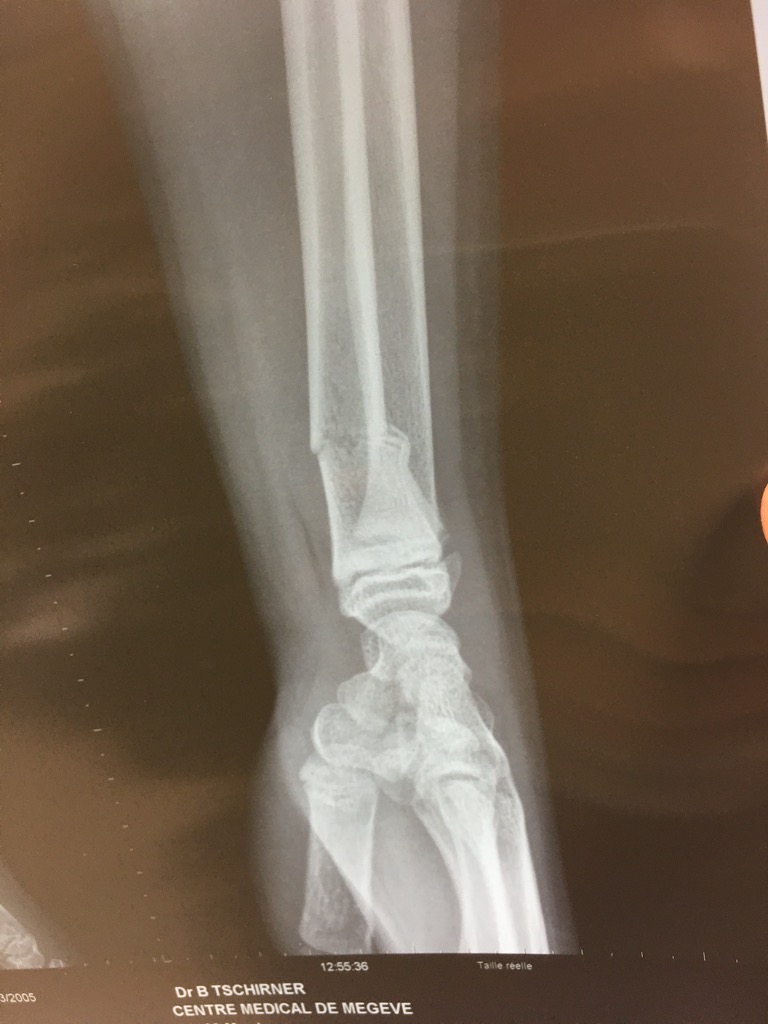

![]() Célian a voulu faire un saut le

jour où tout était verglacé ... ça fait un peu mal

![]() Réduction de fracture au centre

medical de Mégève.

![]() Après un peu de gaz hilarant

|